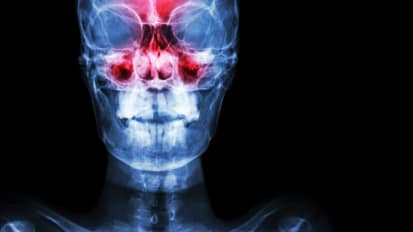

Caring for Patients with Sinonasal Tumors

Johns Hopkins is one of the highest volume centers in the country for these rare cancers.

Rhinology Research Thrives at Johns Hopkins

Faculty members investigate the connection between loss of smell and frailty with age; how a molecule from nasal polyps destroys certain immune cells; new treatments for olfactory neuroblastoma; and more.